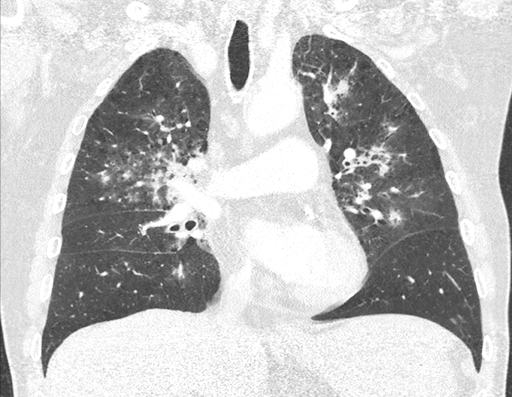

Bildgebung:

Im Röntgenbild zeigen sich rechtsbetonte, bilateral konfluierende Infiltrate. Im CT des Thorax zeigen sich apikal betonte bronchiozentrische Konsolidierungen mit milchglasartigen Verdichtungen und Bronchialwandverdickungen.